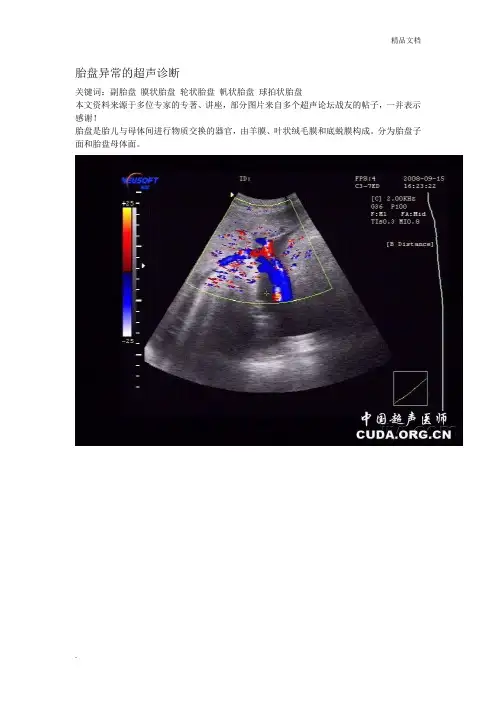

胎盘异常的超声诊断关键词:副胎盘膜状胎盘轮状胎盘帆状胎盘球拍状胎盘本文资料来源于多位专家的专著、讲座,部分图片来自多个超声论坛战友的帖子,一并表示感谢!胎盘是胎儿与母体间进行物质交换的器官,由羊膜、叶状绒毛膜和底蜕膜构成。

分为胎盘子面和胎盘母体面。